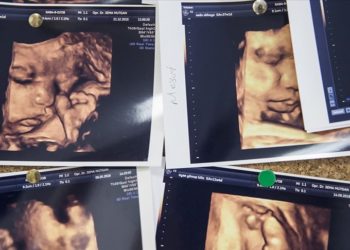

DetayAntalya Eğitim ve Araştırma Hastanesi'nde Genel Cerrahi Uzmanı Prof. Dr. Uzer Küçüktülü ve eşi Radyasyon Onkoloji Uzmanı Doç. Dr. Eda...